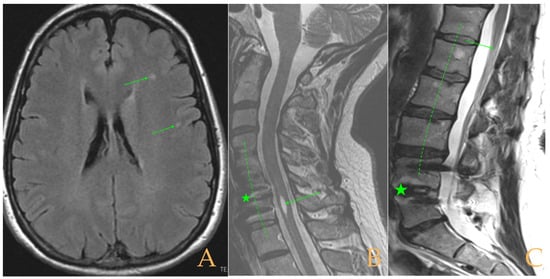

The MRI showed (Figure 9): descent of the cerebellar tonsils, ischemic foci in the white matter of the cerebral hemispheres, and oedema in the optic nerve sheaths. Kyphosis of the cervical spine (especially C5-C6-C7). Tense aspect of the cervical spinal cord. Disc disease: C3-C4-C5-C6-C7-T1. Ischemia and cervical and thoracic oedema. Straightening and scoliosis of the thoracic spine. Lumbar lordosis straightening. Conus medullaris at the level of the middle third of L1. Postsurgical changes in L4-L5 (disc prosthesis). The full-spine X-rays showed cervical, thoracic, and lumbar scoliosis, with the biggest curve being dextroconvex of wide radius in the thoracic and lumbar region.

Figure 9. Imaging of patient 9. A: MRI of the posterior fossa, descent of the cerebellar tonsils (arrow), and increased supracerebellar space (star); B: straightening of the cervical spine (interrupted line) and suboccipital craniectomy with C1 laminectomy (star); and C: conus medullaris at the level of the middle third of L1 (arrow) and L4L5 disc prosthesis (star).